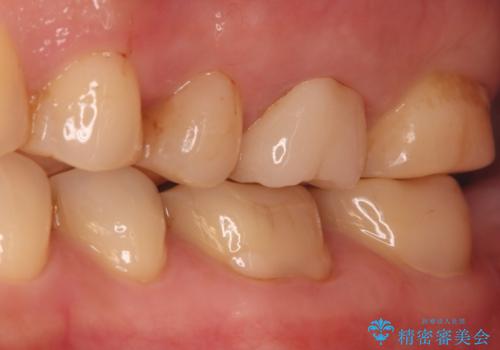

- 右上の歯の痛みを主訴にご来院されました。精密な診査の結果、虫歯が深く進行し、歯の神経(歯髄)にまで炎症が及んでいると診断。このままでは痛みが治まらず、歯を失うリスクもあるため、まず痛みの原因である感染した神経を取り除く根管治療を提案しました。根管治療によって歯の土台を整えた後、歯の破折を防ぎ長期的に機能させるため、**クラウン(被せ物)**を装着して修復する治療計画を立案しました。

治療はまず、感染源を徹底的に除去する根管治療から開始しました。治療の精度を高めるため、ラバーダムや顕微鏡などを使用し、根管内を丁寧に清掃・消毒。これにより、痛みの原因を根本から取り除きました。

根管治療が完了し、歯の内部が清潔で安定した状態になった後、歯を保護し、強い咬合力に耐えられるよう**クラウン(被せ物)**を装着しました。クラウンは、患者様の希望や咬み合わせの状態に応じて、機能性・審美性に優れた素材を選択し、精密に作製しました。

この一連の治療により、長年の痛みが解消されるとともに、修復した歯の強度と機能が回復。安心して食事を楽しめる奥歯を取り戻していただけました。